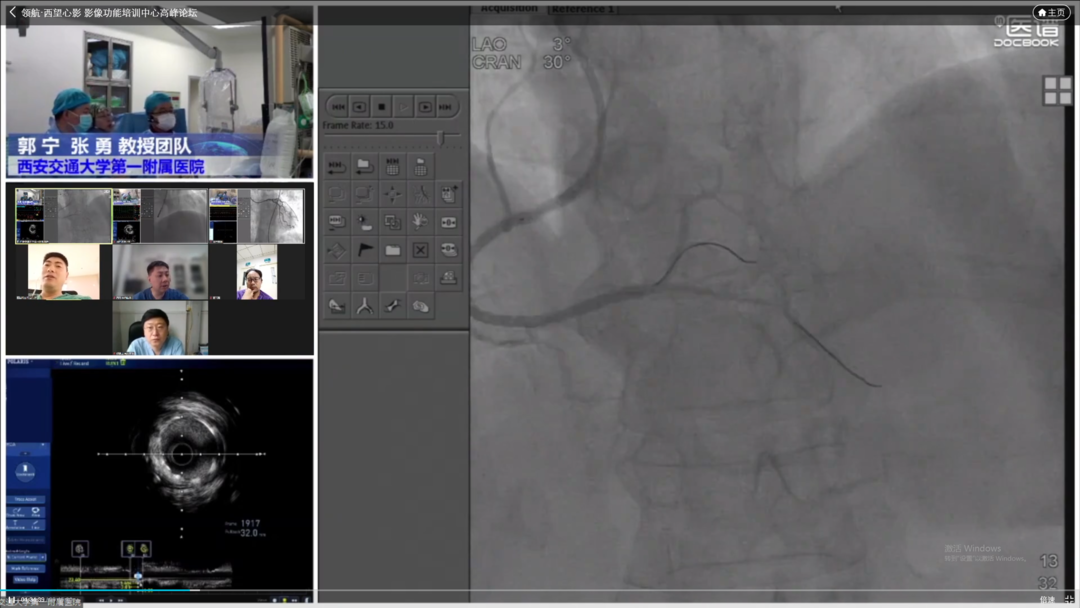

COE卓越中心成立旨在实现头部、地市、县域各医疗中心的联动,实现远程会诊与指导交流。疫情虽然隔绝各地区线下交流,但技术持续发展,远程需求快速增长,必将成为未来发展大趋势。其次希望通过COE中心将多年发展的影像数据进行收集整理发掘更多价值。第三是标准化培训体系建立,既可开展线上远程教学又可在疫情缓解时线下手把手教学,实现上下实时互动。波士顿科学始终对国内影像学与功能学技术的发展充满信心,也希望在波科本土化的进程中,与中国专家共同促进技术创新,服务广大中国患者。会议期间,四川大学华西医院、西安交通大学第一附属医院、南方医科大学南方医院、新疆医科大学第一附属医院、宁夏医科大学总医院心脑血管病医院联袂呈现17例高质量手术直播,所有与会专家各抒己见,畅谈影像技术实战应用。其中四川大学华西医院何森教授带来IVUS指导下LAD重度狭窄伴钙化手术一例。陈勇教授演示一例IVUS指导下的多支血管病变手术;周名纲教授演示一例一月内二次处理的多支病变复杂手术。王勉教授演示一例IVUS指导下逆向开通LAD慢性次全闭塞手术;黄宝涛教授带来了一例IVUS指导下旋磨处理LAD严重钙化病变;李晨教授演示了一例IVSU指导下开通无残端CTO病变的病例。西安交通大学第一附属医院郭宁、张勇教授团队带来造影剂过敏患者PCI治疗,通过IVUS不仅明确病变部位的斑块性质及血管解剖情况,同时确定支架落脚点位置及支架选择。最后在IVUS指导下顺利植入三枚支架,充分展示IVUS对指导低造影剂PCI的临床价值。由南方医科大学南方医院修建成、韩渊、梁鸿彬教授团队带来IVUS指导前降支CTO无残端的病例则先后在对角支、间隔支行IVUS找到前降支开口残端,同时IVUS显示,前降支开口后走行与间隔支夹角较小,近乎平行走行。明确解剖特点后果断决定逆向策略,最终在IVUS指导下,逆向导丝成功进入前降至病变部位远端建立导丝轨道,手术迎来完美结果。宁夏医科大学总医院心脑血管病医院仇玉民、胡光欣教授带来一例右冠CTO病例,残端似乎存在微通道,本计划行ADR,首次尝试正向开通时选择波士顿科学Sentai导丝家族Fighter导丝,仇教授提到该款导丝操控性极佳,头端硬度1.5g,外径0.09"直接通过微通道越过病变部位到达右冠远端,成功建立轨道。正确选择导丝取得开门红后,在IVUS指导下顺利植入一枚支架,迅速完成了这例颇具挑战的手术。精彩的手术演示不仅深度传递腔内影像学与功能学指导下优化PCI治疗的理念,更详细阐述IVUS的规范操作和读图技巧,在理论与实践两方面,实现知行合一。